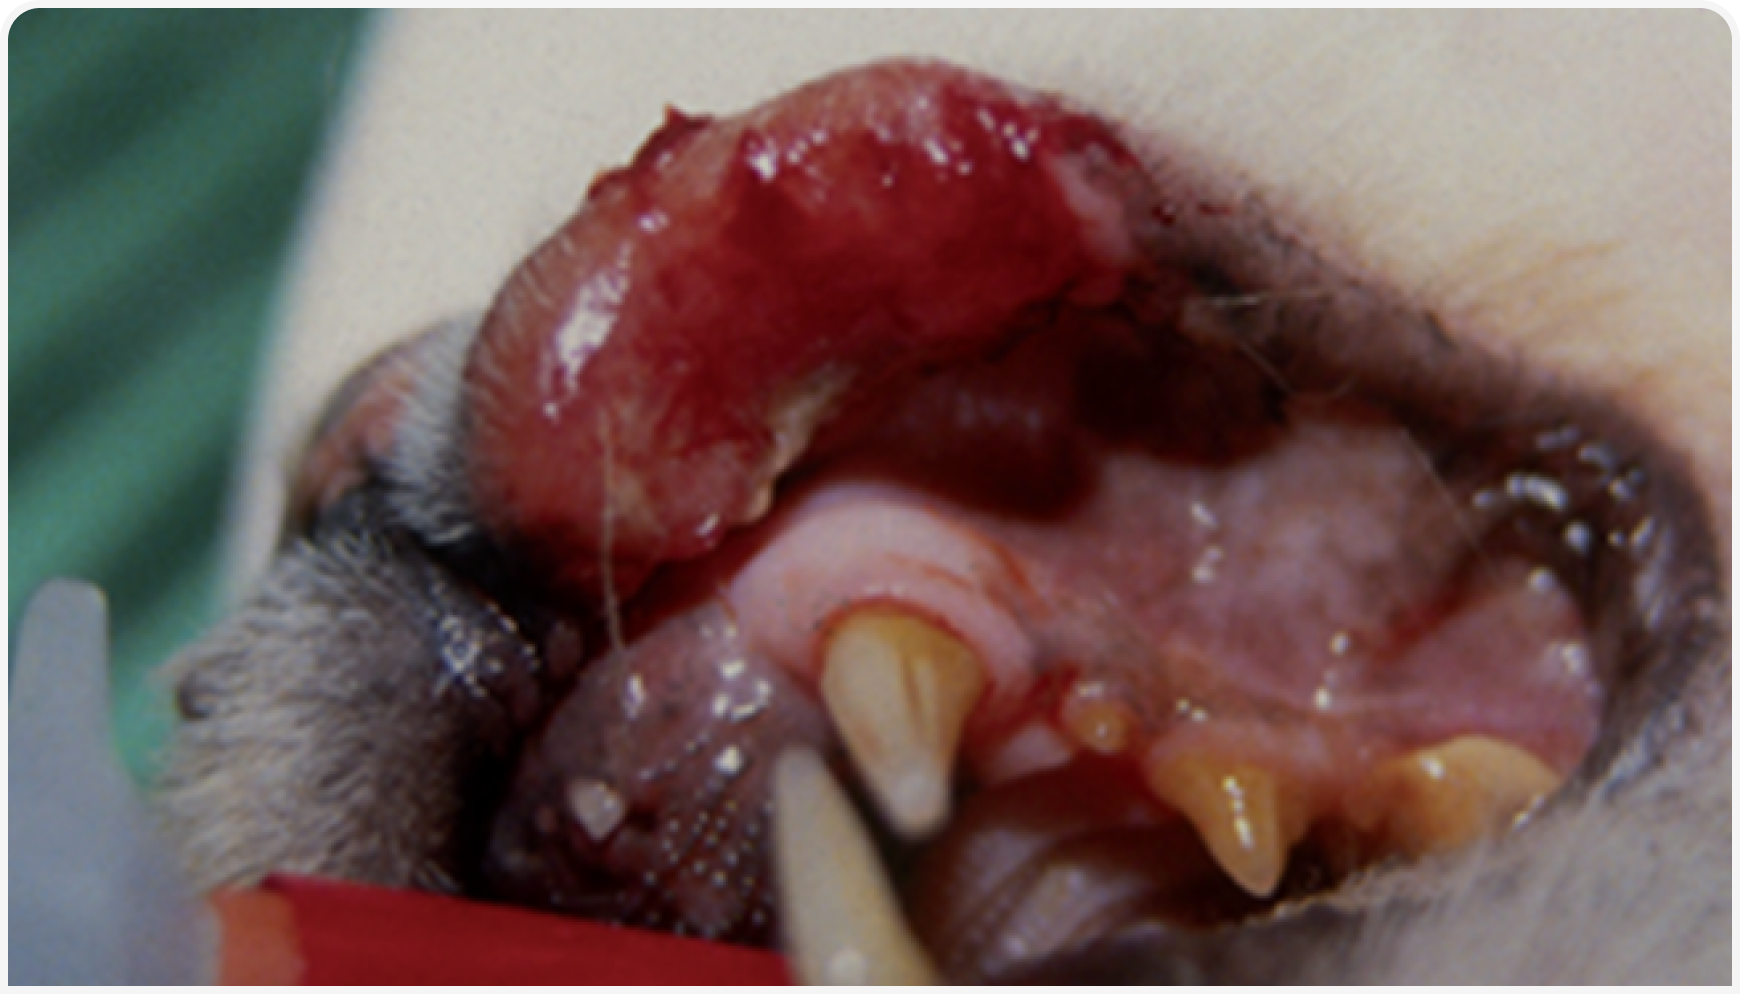

Лимфома кожи кошек — опухоль редкая, и о клинических проявлениях, лечении и прогнозе двух форм этого заболевания публикаций мало. Тем не менее при ведении пациента с подозрением на лимфому кожи кошек ключевое значение для улучшения прогноза имеет ранняя диагностика; по возможности в начале диагностического обследования следует проводить биопсию кожи. Стандарт лечения в настоящее время не определен и, несомненно, требует дальнейших исследований, но обзор литературы показывает, что кошек лечили системной химиотерапией, и, где это уместно, применяли мультимодальный подход для оптимизации ответа на лечение. Кроме того, наряду с основной терапией следует начать симптоматическое лечение для повышения качества жизни, особенно на фоне паллиативной терапии.